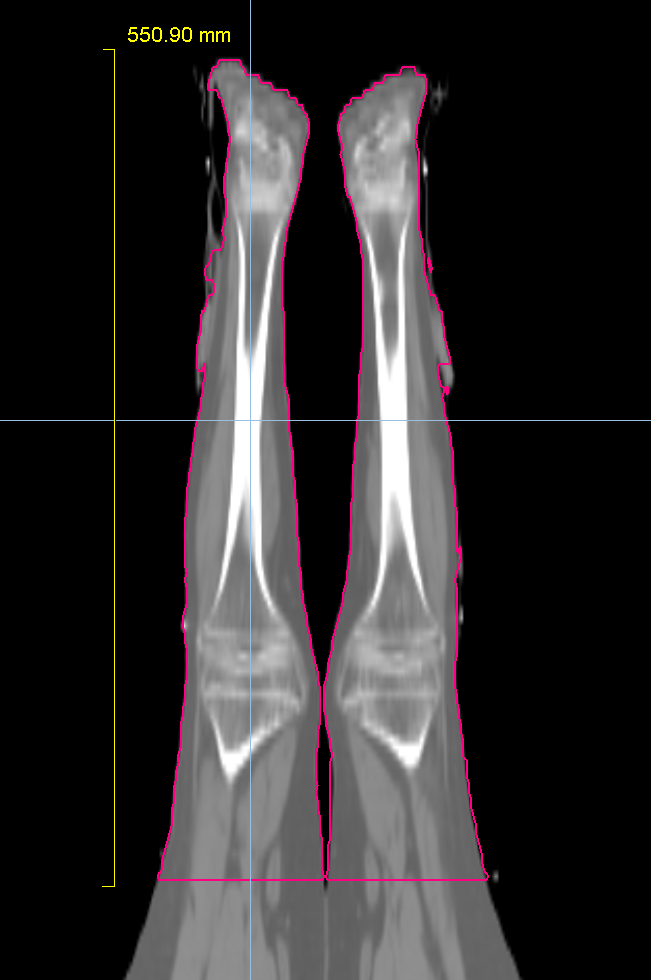

Planning CT Images

PTV(s) Volume, Length

27500 cc, 84 cm

5440 cc, 64cm